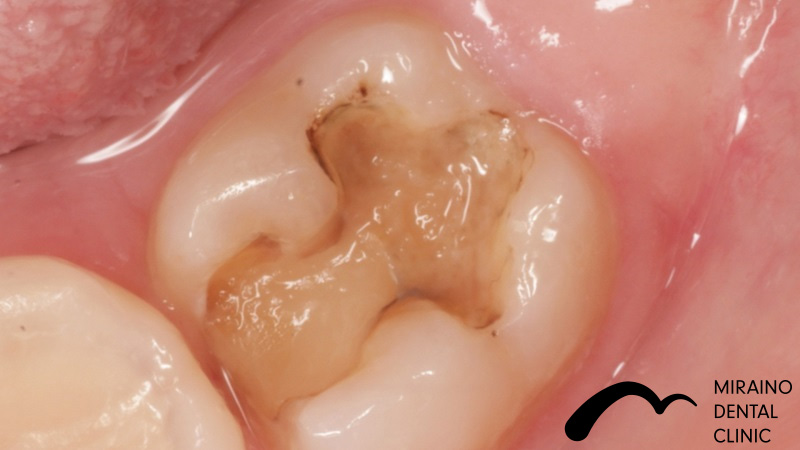

Case1

| 施術名 | 詰め物・メタルフリーインレー |

| 施術の概要 | 定期検診の際に、レントゲンを撮影した際に 5年前以上に治療した銀歯に隙間があることを衛生士が見つけました。 沁みる、噛むと痛いといった症状はありませんでしたが 次回再発した際は神経を取らないといけなくなる可能性が高いため 、 なるべく再発しにくい歯科治療を希望され、メタルフリーインレーによる修復治療を行いました。 |

クリックして詳細を表示

| 施術の内容 | 銀歯は歯より硬すぎる、歯を腐食させる作用があることから約5年で再発すると言われています。 ラバーダムを用いて唾液による接着不良のリスクを排除し完全に水分を排除した状態でムシ歯治療を行います。 型取りを行い、技工士によって汚れの付きにくいセラミックで形を再現している。 |

| 1歯あたりの治療費 | 1歯:50,000円 |